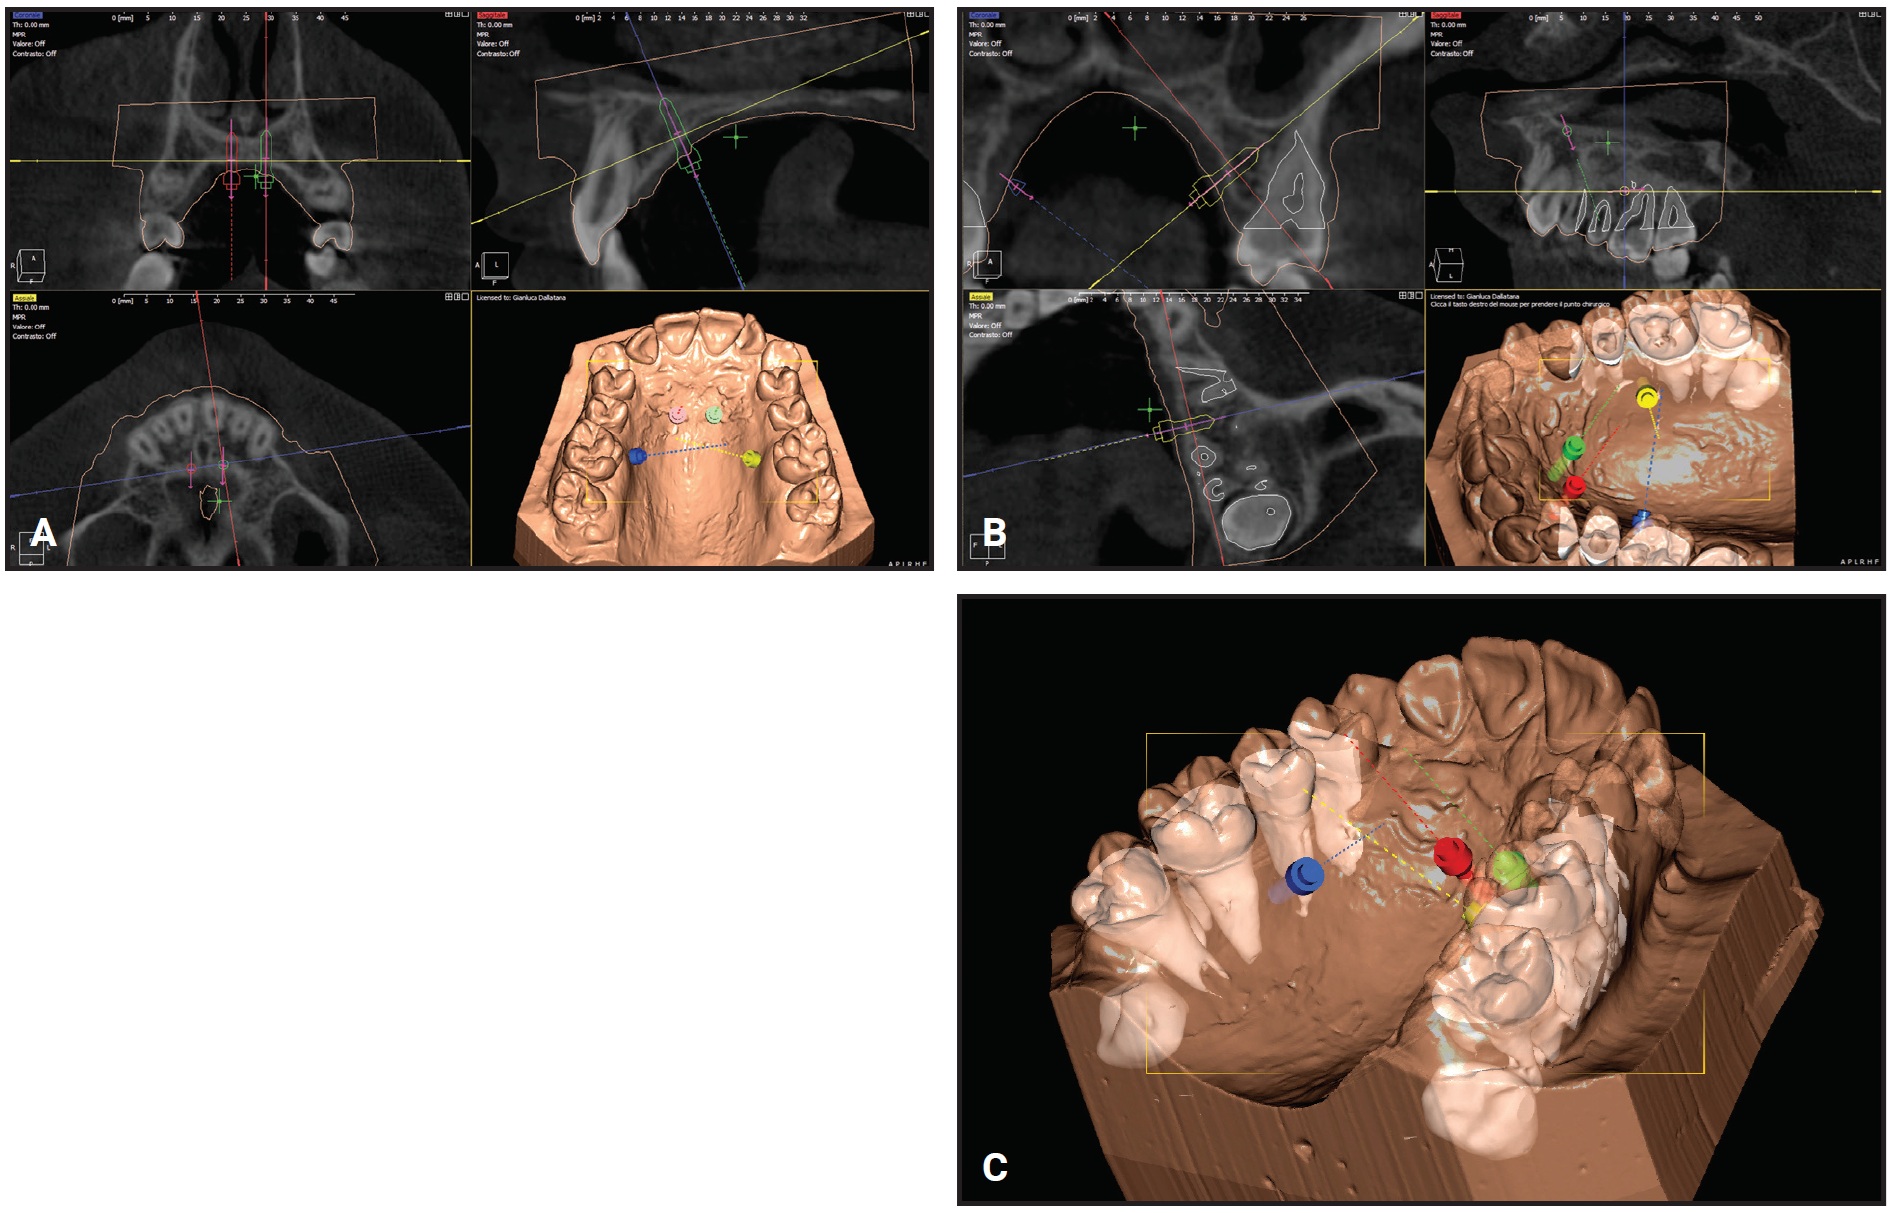

Using the procedure described above, a CBCT was superimposed on the digital model (Fig. 2).

Fig. 2 Case 1. Overlay of cone-beam computed tomography (CBCT) scan and digitized model for planning of anterior and posterior mini-implant locations.

Analysis of the CBCT image indicated sufficient bone for two 9mm × 2mm mini-implants† in the anterior palate lateral to the suture. Because the posterior paramedian bone was insufficient for skeletal anchorage, we decided to place two 7mm × 2mm mini-implants in the alveolar ridge between the roots of the second premolars and first molars. After overlaying the virtual model and the CBCT, the positions of the anterior and posterior mini-implants were digitally planned. The insertion guides were digitally produced (Fig. 3), and the mini-implants and Quadexpander were inserted at the same appointment (Fig. 4A,B).